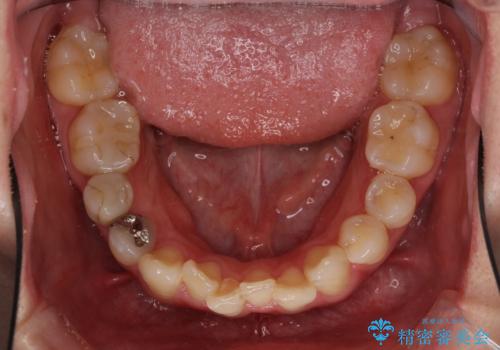

- 上下のデコボコと奥歯の咬みにくさを気にして来院された患者様です。

上顎骨の幅が下顎骨よりも小さいので、拡大装置により骨幅を広げて上下関係を改善し、その後インビザラインにて歯並びを整えることとしました。